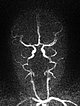

Dynamische, kontrastmittelunterstützte MR-Angiographie des Schädels und der hirnversorgenden Gefäße. In der ganz früharteriellen Phase (A) noch kein Enhancement der Läsion am linken Auge.

Dynamische, kontrastmittelunterstützte MR-Angiographie des Schädels und der hirnversorgenden Gefäße. In der arteriellen Phase 5 s später (B) bereits starkes Enhancement des Tumors am linken Auge.

Dynamische, kontrastmittelunterstützte MR-Angiographie des Schädels und der hirnversorgenden Gefäße. In der venösen Phase (C) weiterhin bestehendes starkes, homogenes Enhancement, venöse Drainage über die Vena facialis und Vena jugularis externa links.